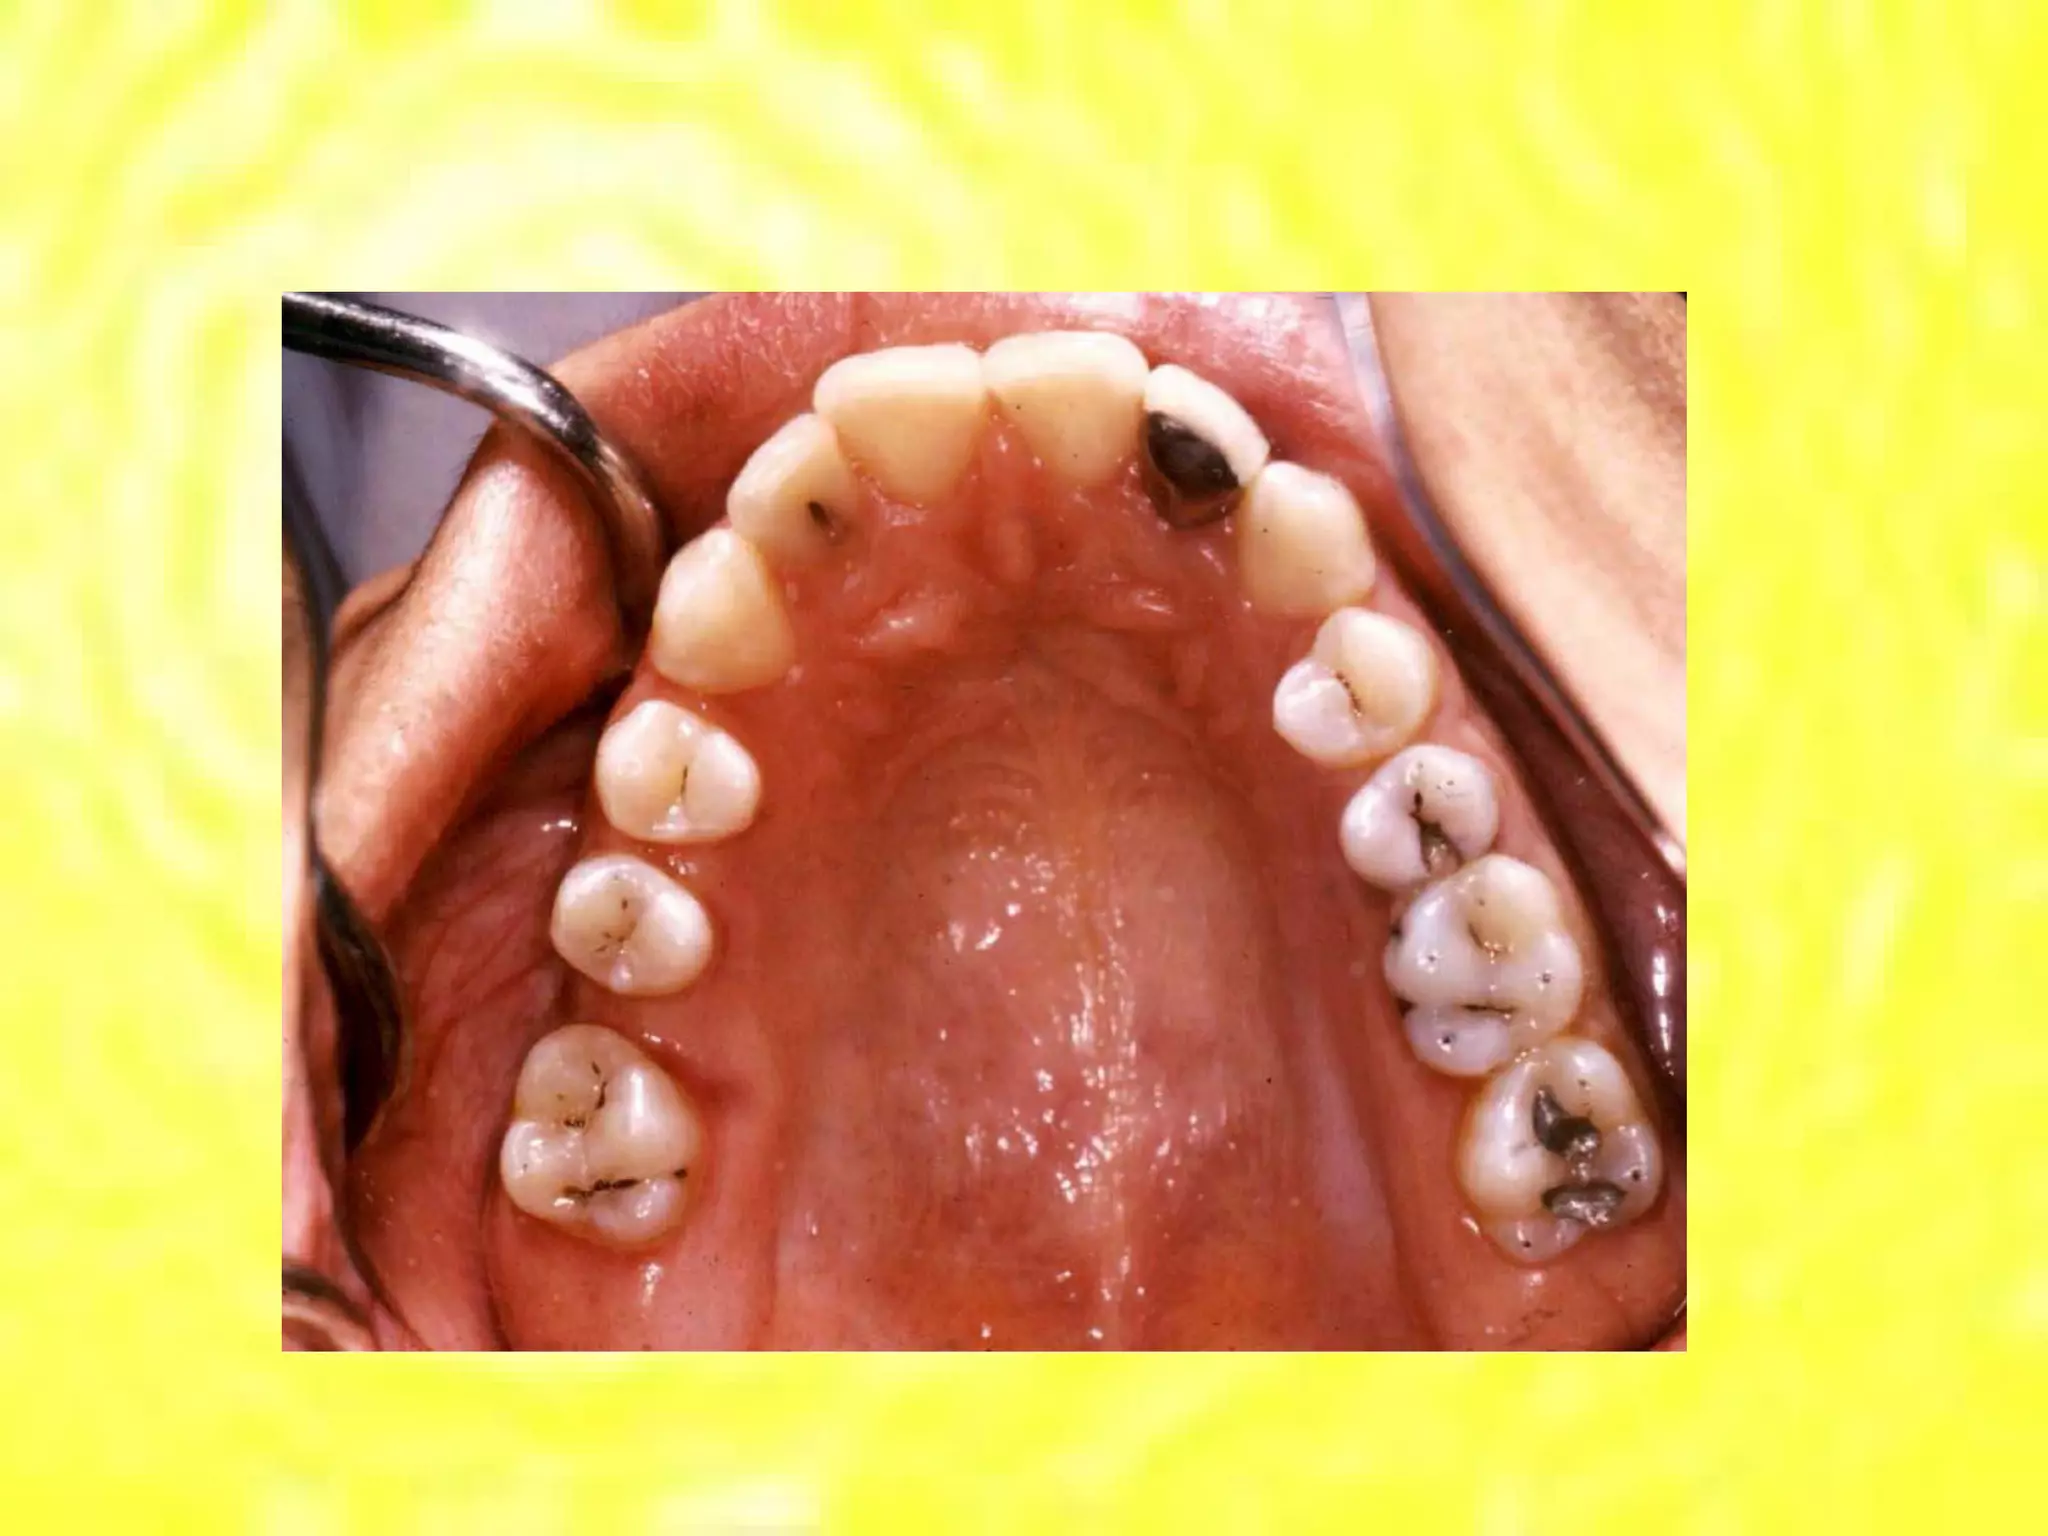

Dental Caries •  Dental caries is an infectious microbiological disease of the teeth that results in localized  dissolution and  destruction  of the calcified tissue, caused by the action of microorganisms  and fermentable carbohydrates.

Dental Caries Characterized by : –  Demineralization  of the mineral portion of  enamel+ dentine. –  Disintegration of their  organic material. –  As the disease approach the pulp may result in death of the pulp. –  It can be arrested or prevented.

Classification of Decay •  Based on anatomy of the surface involved •  Pit and fissures carious lesions – Class I  –  begin in the depth of pits and fissures in enamel – Occur: • Occlusal surface of post. teeth •  Lingual fossa of maxillary incisors

Smooth Surface Carious Lesions •  Occur on the smooth surface of the anatomic crown of a tooth in area that are most inaccessible to the natural cleansing action of the lips, cheeks and tongue. –  Proximal surfaces  –  class II –  Facial and lingual surfaces  – class III ,  IV ,  V –  Root caries on  cementum

Classification of Decay• Based on anatomy of the surface involved • Pit and fissures carious lesions – Class I – begin in the depth of pits and fissures in enamel – Occur: • Occlusal surface of post. teeth • Lingual fossa of maxillary incisors

Smooth Surface CariousLesions • Occur on the smooth surface of the anatomic crown of a tooth in area that are most inaccessible to the natural cleansing action of the lips, cheeks and tongue. – Proximal surfaces – class II – Facial and lingual surfaces – class III , IV , V – Root caries on cementum